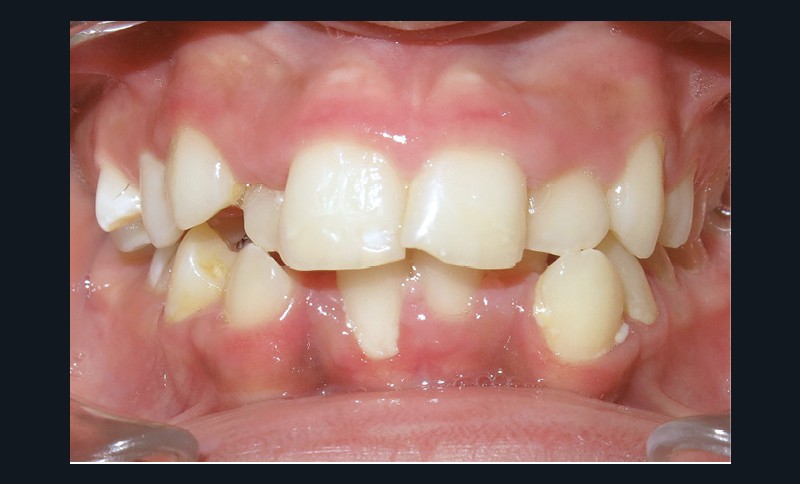

Le niveau d’hygiène est alarmant, car le rituel du brossage des dents n’est pas instauré dans la famille. Des caries se sont développées sur les dents temporaires et en ont imposé l’extraction. Les molaires permanentes ont dérivé mésialement, réduisant l’espace disponible sur l’arcade.

En denture adulte, la DDM est majeure avec un déficit de place estimé de 13 mm à la mandibule. Les lésions carieuses ont aussi touché les premières molaires permanentes maxillaires. La 26 a été avulsée et la 27 a pris sa place. Côté controlatéral, la 16 est fortement délabrée, rendant impossible sa conservation. Les molaires ayant plus mésialé à l’arcade mandibulaire, les rapports occlusaux sont de classe III. Les incisives sont versées vers l’avant, mais nous pouvons considérer qu‘il s’agit d’une biproalvéolie ethnique. Du point de vue squelettique, le patient présente une classe II squelettique par rétromandibulie sur un schéma facial hyperdivergent (fig. 1a-j).